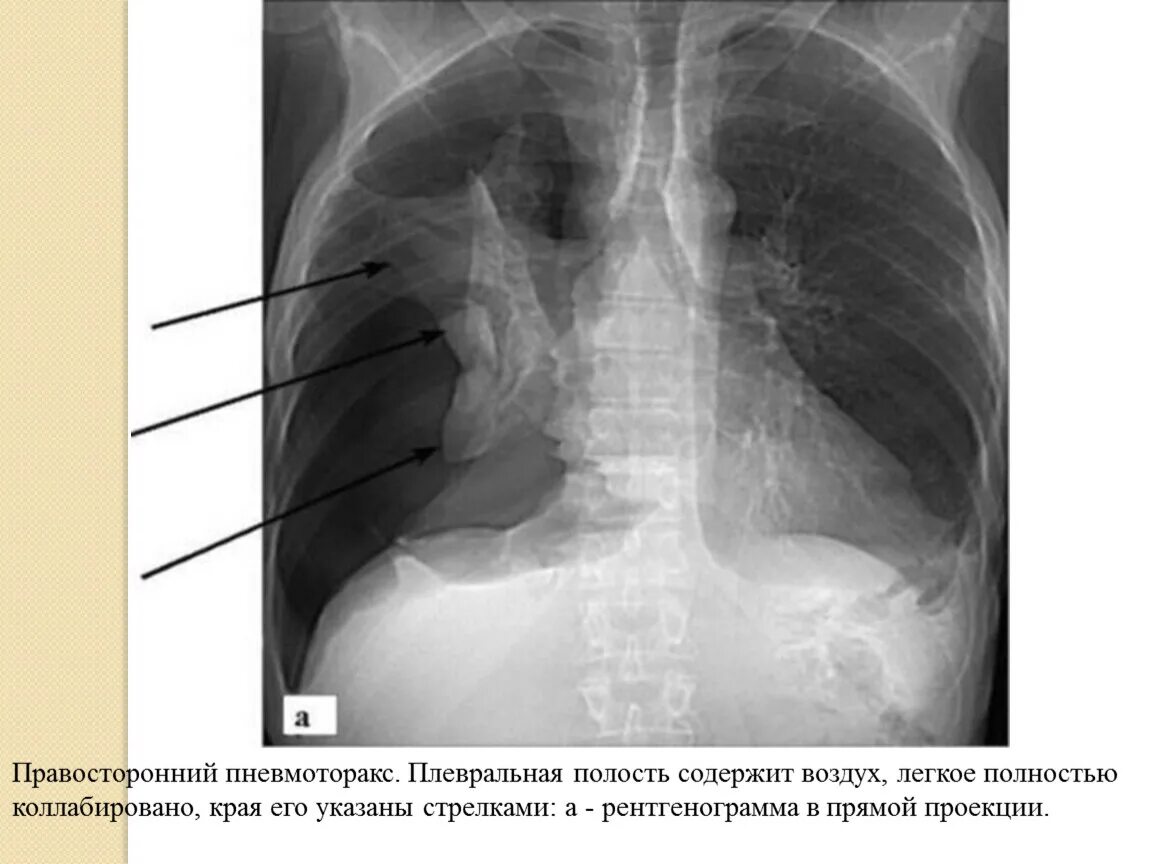

Коллабированное легкое при пневмотораксе